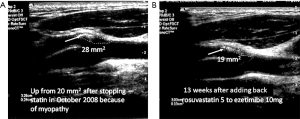

In 2003, we implemented a new approach to vascular prevention: instead of being content with target levels of risk factors such as blood pressure and low-density lipoprotein cholesterol (LDL-C), the target of therapy was to stop progression of plaque or achieve regression of plaque (14). The process is described in Table 1. By 2010 it was apparent that this approach had markedly reduced the risk of patients with ACS, and the proportion of patients with plaque regression vs. progression had reversed: now only about a quarter of patients had plaque progression, and about half had regression (14). After implementing “treating arteries” the percent of patients with microemboli on TCD, a strong predictor of risk discussed below, declined from 12.6% to 3.7% of patients, and the rate of carotid plaque progression declined significantly. More importantly, the 2-year risk of stroke and myocardial infarction declined by more than 80% (15). Plaque area changes within a clinically meaningful time frame; even plaque area changes within 3 months (16) (Figure 1), so can be used to treat patients.